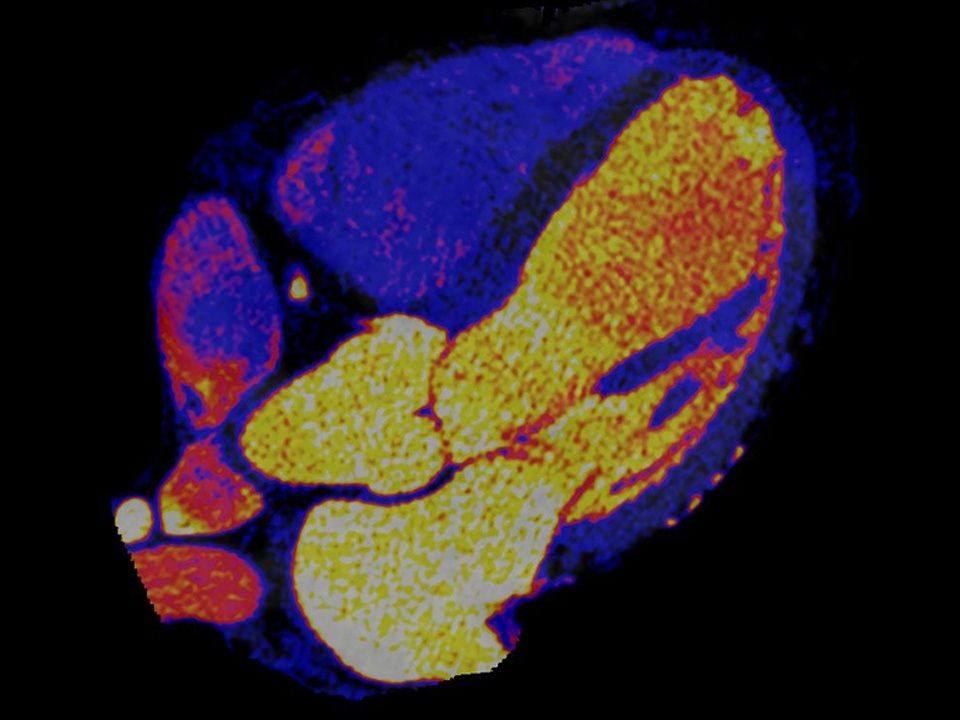

CT DE Heart PBV

Reveal perfusion defects with only one scan.